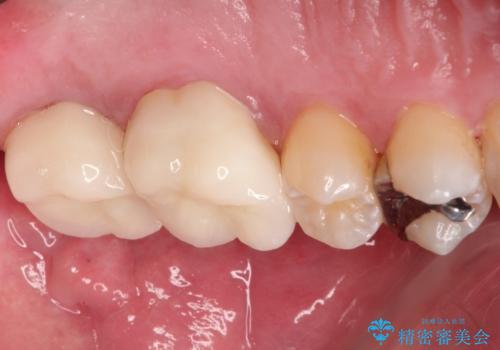

目立つ金歯を自然な色のオールセラミックへ

- 矯正の治療後に目立つ金歯を白くしたいとのことで治療することとなりました。

左上の奥歯に大きな金歯と、その後ろの歯が矯正治療用の仮歯が装着されていました。

これらの歯にオールセラミッククラウンを装着することとなりました。